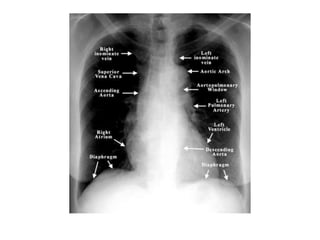

This document provides an overview of interpreting chest x-rays and identifies several key factors. It discusses the importance of inspiration, penetration, and rotation in obtaining a technically quality radiograph. It also outlines different views of chest x-rays including PA, AP, and lateral views. Finally, it identifies several anatomical structures that should be evaluated when interpreting a chest x-ray such as the lungs, heart, diaphragm, bones, and soft tissues.